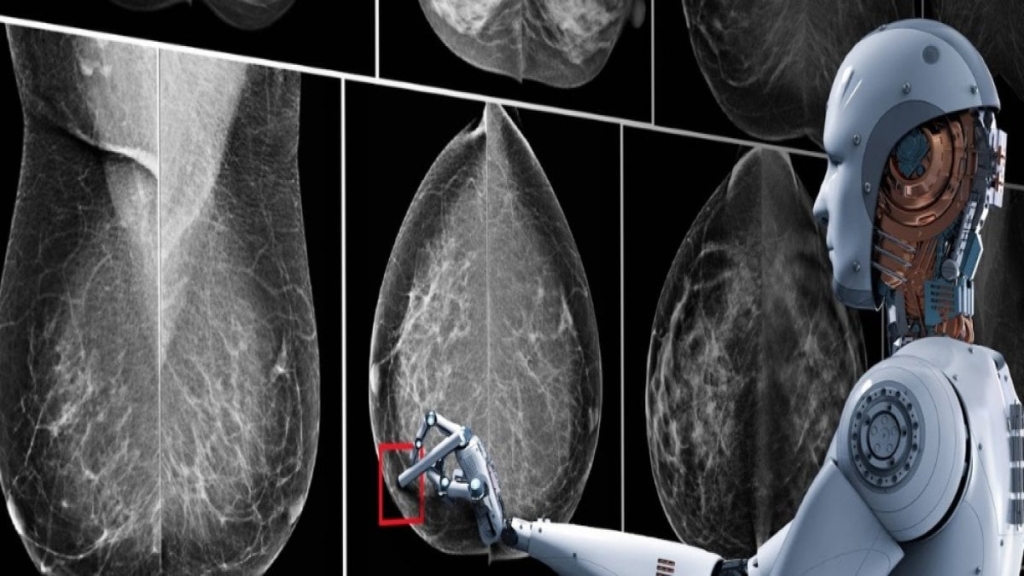

Yapay Zeka ve Kanser Teşhisindeki Yenilikler

Yapay zekanın kanser teşhisinde sunduğu yenilikler, erken tanı ve kişiye özel tedavi süreçlerine önemli katkılarda bulunuyor. Peki, bu teknoloji kanser teşhisinde nasıl kullanılmakta ve mevcut bilimsel araştırmalar neler gösteriyor? Uzman görüşleri ve bilimsel veriler ışığında bu sorulara yanıt arıyoruz.

Kanser Teşhisinde Yapay Zekanın Önemi

Yapay zeka, kanser teşhisi süreçlerinde görüntüleme teknikleri ve büyük veri analizinden yararlanarak kritik bir rol üstlenmektedir. Bu teknoloji, kan örnekleri ve tıbbi görüntülerdeki anormal hücreleri saniyeler içinde tespit etme yeteneğine sahiptir. Bu hızlı ve hassas tanımlama becerisi, özellikle hızlı hücre çoğalması gösteren kanser türleri için hayati bir öneme sahip.

Bir uzmanın ifadeleriyle, "Yenilikçi yapay zeka platformlarıyla kanser hücreleri saniyeler içinde tespit ediliyor."

Bilimsel Araştırmaların Sonuçları

Bilim dünyası, yapay zekanın kanser teşhisindeki etkinliğini destekleyen birçok araştırma bulgusu sunmakta. Örneğin, bir üniversitede geliştirilen yapay zeka modelleri, kanserin daha hızlı ve hassas tanısını mümkün kılarken, tıbbi görüntülerdeki tümör özelliklerini tespit ederek, doktorların daha sağlıklı ve hızlı kararlar almalarına yardımcı oluyor.

Uzmana Görüşler ve Klinik Uygulamalar

Uzmanlar, yapay zekanın kanser teşhisine sağladığı katkıları dile getirmekte. Bir uzman, "Yapay zeka destekli programlar, geleneksel görsel yorumlamanın yanında hekimlerin uzmanlık ve tecrübesini tamamlayarak alternatif fikirler sunabiliyor," şeklinde açıklamada bulunmuştur. Yapay zeka algoritmaları, tümör tanı ve tedavi süreçlerinin kişiye özel hâle gelmesine yardımcı olmaktadır.

Erken Teşhis ve Kişiye Özel Tedavi

Yapay zeka, erken tanı koyma ve kişiye özel tedavi planlama aşamalarında da kritik bir rol oynamaktadır. Bu destekleyici sistemler, kan örneklerinde anormal hücreleri yüksek doğruluk oranlarıyla ayırt edebilmekte ve bu sayede doktorların daha hızlı karar vererek tedaviye en erken aşamada başlamalarına olanak tanımaktadır.

Teknolojinin sunduğu bu gelişmeler, kanser teşhisinde devrim niteliğinde ilerlemeler sağlamaktadır. Bilimsel araştırmalar ve uzman görüşleri, yapay zekanın erken tanı ve kişiye özel tedavi süreçlerine katkı sağladığını gözler önüne sermekte. Yapay zeka, kanser hücrelerini hızlı ve hassas bir şekilde tespit ederek, hastaların tedavi süreçlerini optimize etmeye devam etmektedir.